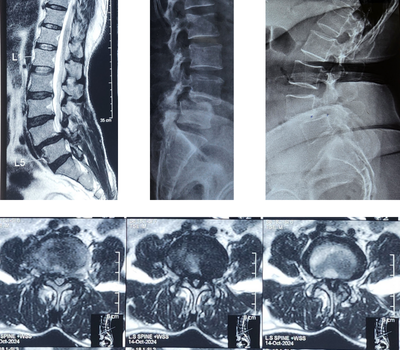

- MRI and X-ray reports confirmed a Grade 3 L4-L5 slipped disc, causing severe nerve compression and lumbar canal stenosis.

Radiological Investigations for Lumbar Spinal Treatment:

- X-Ray of Lower Spine : Showed vertebra misalignment at L4-L5 (spondylolisthesis) – a condition where one vertebra slips over the one below, often causing chronic lower back pain and nerve-related symptoms. This confirmed the need for targeted lumbar spinal treatment to prevent further nerve compression and mobility issues.

- MRI Scan of Lower Back and Full Spine : Revealed signs of age-related disc degeneration (spondylosis) in the lower and cervical spine. Also showed Grade 3 L4-L5 vertebra slip, with the disc pressing on the spinal cord and nerve roots, causing spinal canal narrowing. These findings clearly indicated the need for advanced lumbar spinal treatment to relieve nerve pressure and restore function.

- Post-Surgery X-Ray : Confirmed successful spinal alignment using orthopedic implants following minimally invasive lumbar spinal treatment, aimed at stabilizing the spine and relieving nerve compression.